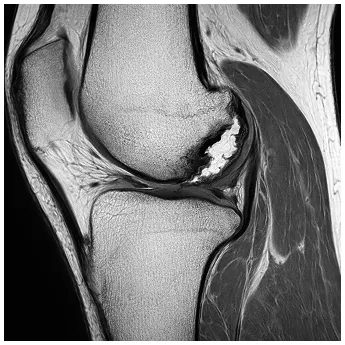

診断

半月板損傷かどうかを調べるには、膝の動きや痛みの出方を確認するいくつかの徒手検査があります。代表的なものとして、ApleyテストやMcMurrayテスト、膝を過伸展させるHyperextensionテストなどがあります。また、膝の押したときの痛み(圧痛)も診断の手がかりになります。

半月板はレントゲンでは見えないため、詳しく状態を確認するにはMRI検査が必要です。MRIを使うことで、損傷の形や範囲を正確に把握でき、適切な治療方法を決める際に非常に役立ちます。

MRI

半月板が水平に断裂している様子を示したMRI写真

長年膝の痛みがあり、ヒアルロン酸注射やPRP治療を受けても改善しない場合、軟骨や半月板の損傷が進行していることがあります。特に半月板が水平断裂していると、膝の曲げ伸ばしで損傷部分が挟まり、痛みで関節の動きが制限されます。